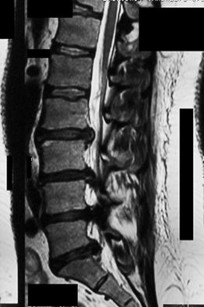

A 65-year-old female presents with neurogenic claudication and lower back pain. Radiographs reveal a grade I L4-L5 degenerative spondylolisthesis. Which of the following anatomical features is most characteristic of degenerative spondylolisthesis compared to isthmic spondylolisthesis?

Options:

Correct Answer: Sagittal orientation of the facet joints

Explanation:

Degenerative spondylolisthesis most commonly occurs at L4-L5 and is associated with a more sagittal orientation of the facet joints, which allows for anterior translation as the disc and joints degenerate without a pars defect. Isthmic spondylolisthesis involves a pars interarticularis defect, most commonly occurs at L5-S1, and is often associated with higher pelvic incidence.